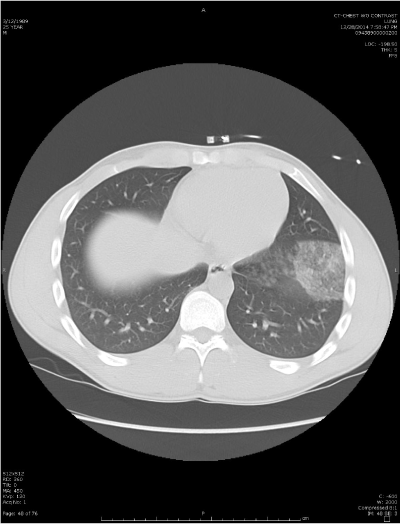

As a follow up to this x-ray, a CT was performed (figure 2), which confirmed the presence of the pulmonary contusion.

Figure 2. As a follow up to this x-ray, a CT was performed, which confirmed the presence of the pulmonary contusion.